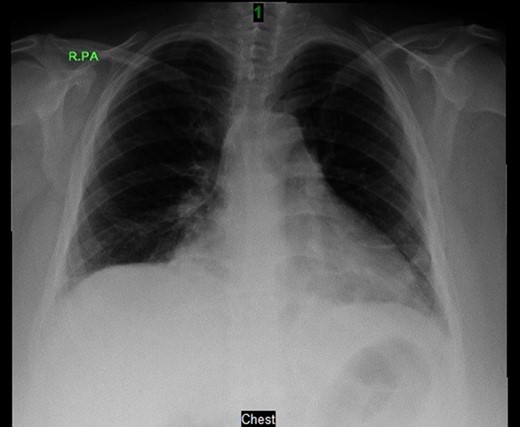

Prior to the surgery patient had symptoms of mild dyspnea, vague abdominal discomfort and an initial evaluation with Chest X Ray revealed bowel gas pattern in the right hemithorax (Fig. 1). A subsequent CAT scan thorax and abdomen revealed a right-sided large morgagni diaphragmatic hernia containing omentum and portion of the transverse colon (Fig. 2). Patient elected to undergo Laparoscopic sleeve gastrectomy and concomitant morgagni diaphragmatic hernia repair. Abdomen was explored laparoscopically which revealed a right sided morgagni diaphragmatic hernia with defect size about 8 × 4 cm, containing omentum, transverse colon and part of the falciform ligament. Contents were reduced successfully taking care not to injure the bowel, falciform ligament partially dissected. A sleeve gastrectomy done. Then the hernial defect was closed primarily by interrupted non absorbable sutures. The closure was then reinforced with a sublay ventralight mesh which was secured using transfascial fixation sutures and with tackers (Fig. 3). The post operative course was unremarkable and the patient was discharged on post operative Day 2 with normal chest X-ray (Fig. 4). At 2 months after surgery the patient was doing well and tolerating solid and liquid diet and no more dyspnea nor GI symptoms.